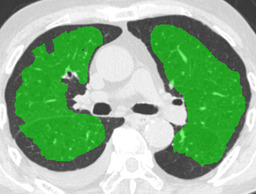

In this paper, we define partial annotation as an annotation format in which only one class is chosen for the annotation and only pixels belonging to the chosen class are annotated per image. For example, in Figure 1(a), although there is ground glass opacity in the image, only consolidation is chosen for annotation and pixels of consolidation are annotated. Partially annotated dataset is less informative for training, however, it is much easier to create compared to fully annotated dataset since annotators only need to focus on one class at a time during the annotation task.

Partially annotated datasets have been utilized previously [8, 9]. In this paper, we propose a new weak supervision technique that fully utilizes partially annotated dataset. Throughout this paper, each DLD pattern is represented or painted in the following colors (CON:cyan, GGO:yellow, HCM:red, EMP:green, NOR:brown.)

Statistics of our dataset are shown in Table 1 and typical images and their annotations for each DLD pattern are shown in Figure 1. In our partially annotated dataset, all the pixels in a slice were manually classified into two classes: dominating DLD pattern and other tissues. In other words, all the pixels in our dataset were assigned one of the labels from either of the two label sets, Lstrong={lCON,lGGO,lHCM,lEMP,lNOR}subscript𝐿𝑠𝑡𝑟𝑜𝑛𝑔subscript𝑙𝐶𝑂𝑁subscript𝑙𝐺𝐺𝑂subscript𝑙𝐻𝐶𝑀subscript𝑙𝐸𝑀𝑃subscript𝑙𝑁𝑂𝑅L_{strong}=\{l_{CON},l_{GGO},l_{HCM},l_{EMP},l_{NOR}\} or Lweak={lCON¯,lGGO¯,lHCM¯,lEMP¯,lNOR¯}subscript𝐿𝑤𝑒𝑎𝑘subscript𝑙¯𝐶𝑂𝑁subscript𝑙¯𝐺𝐺𝑂subscript𝑙¯𝐻𝐶𝑀subscript𝑙¯𝐸𝑀𝑃subscript𝑙¯𝑁𝑂𝑅L_{weak}=\{l_{\overline{CON}},l_{\overline{GGO}},l_{\overline{HCM}},l_{\overline{EMP}},l_{\overline{NOR}}\}. For example, in Figure 1(a), colored pixels were labeled as lCONsubscript𝑙𝐶𝑂𝑁l_{CON} and all the other pixels were labeled as lCON¯subscript𝑙¯𝐶𝑂𝑁l_{\overline{CON}}. In this paper, we call pixels of label lLweak𝑙subscript𝐿𝑤𝑒𝑎𝑘l\in L_{weak} and lLstrong𝑙subscript𝐿𝑠𝑡𝑟𝑜𝑛𝑔l\in L_{strong} as weakly annotated pixels and strongly annotated pixels respectively. Our pixel-wise annotations were created in the following steps. First, up to 3 slices were chosen for the annotation for each HRCT scan and for each slice, one representing DLD pattern was chosen by a radiologist. Second, three radiologists performed pixel-wise binary annotation (e.g. binary annotation between lCONsubscript𝑙𝐶𝑂𝑁l_{CON} or lCON¯subscript𝑙¯𝐶𝑂𝑁l_{\overline{CON}}) for each slice. Finally, the radiologists’ annotations were merged by taking majority classes for each pixel (i.e. pixels labeled as a DLD pattern by more than 2 radiologists became the corresponding DLD pixel). In addition to the DLDs annotation, lung fields were manually segmented under the supervision of radiologists and training and testing were conducted only within the lung fields.

Figure 1: Typical slices for each DLD classes. Slices of HRCT are shown in lung window setting (window-center=-600, window-width=1500) with annotated labels superimposed in transparent colors. Note that even if more than one DLD patterns existed, only one DLD pattern was chosen and annotated for a slice to facilitate the annotation process.